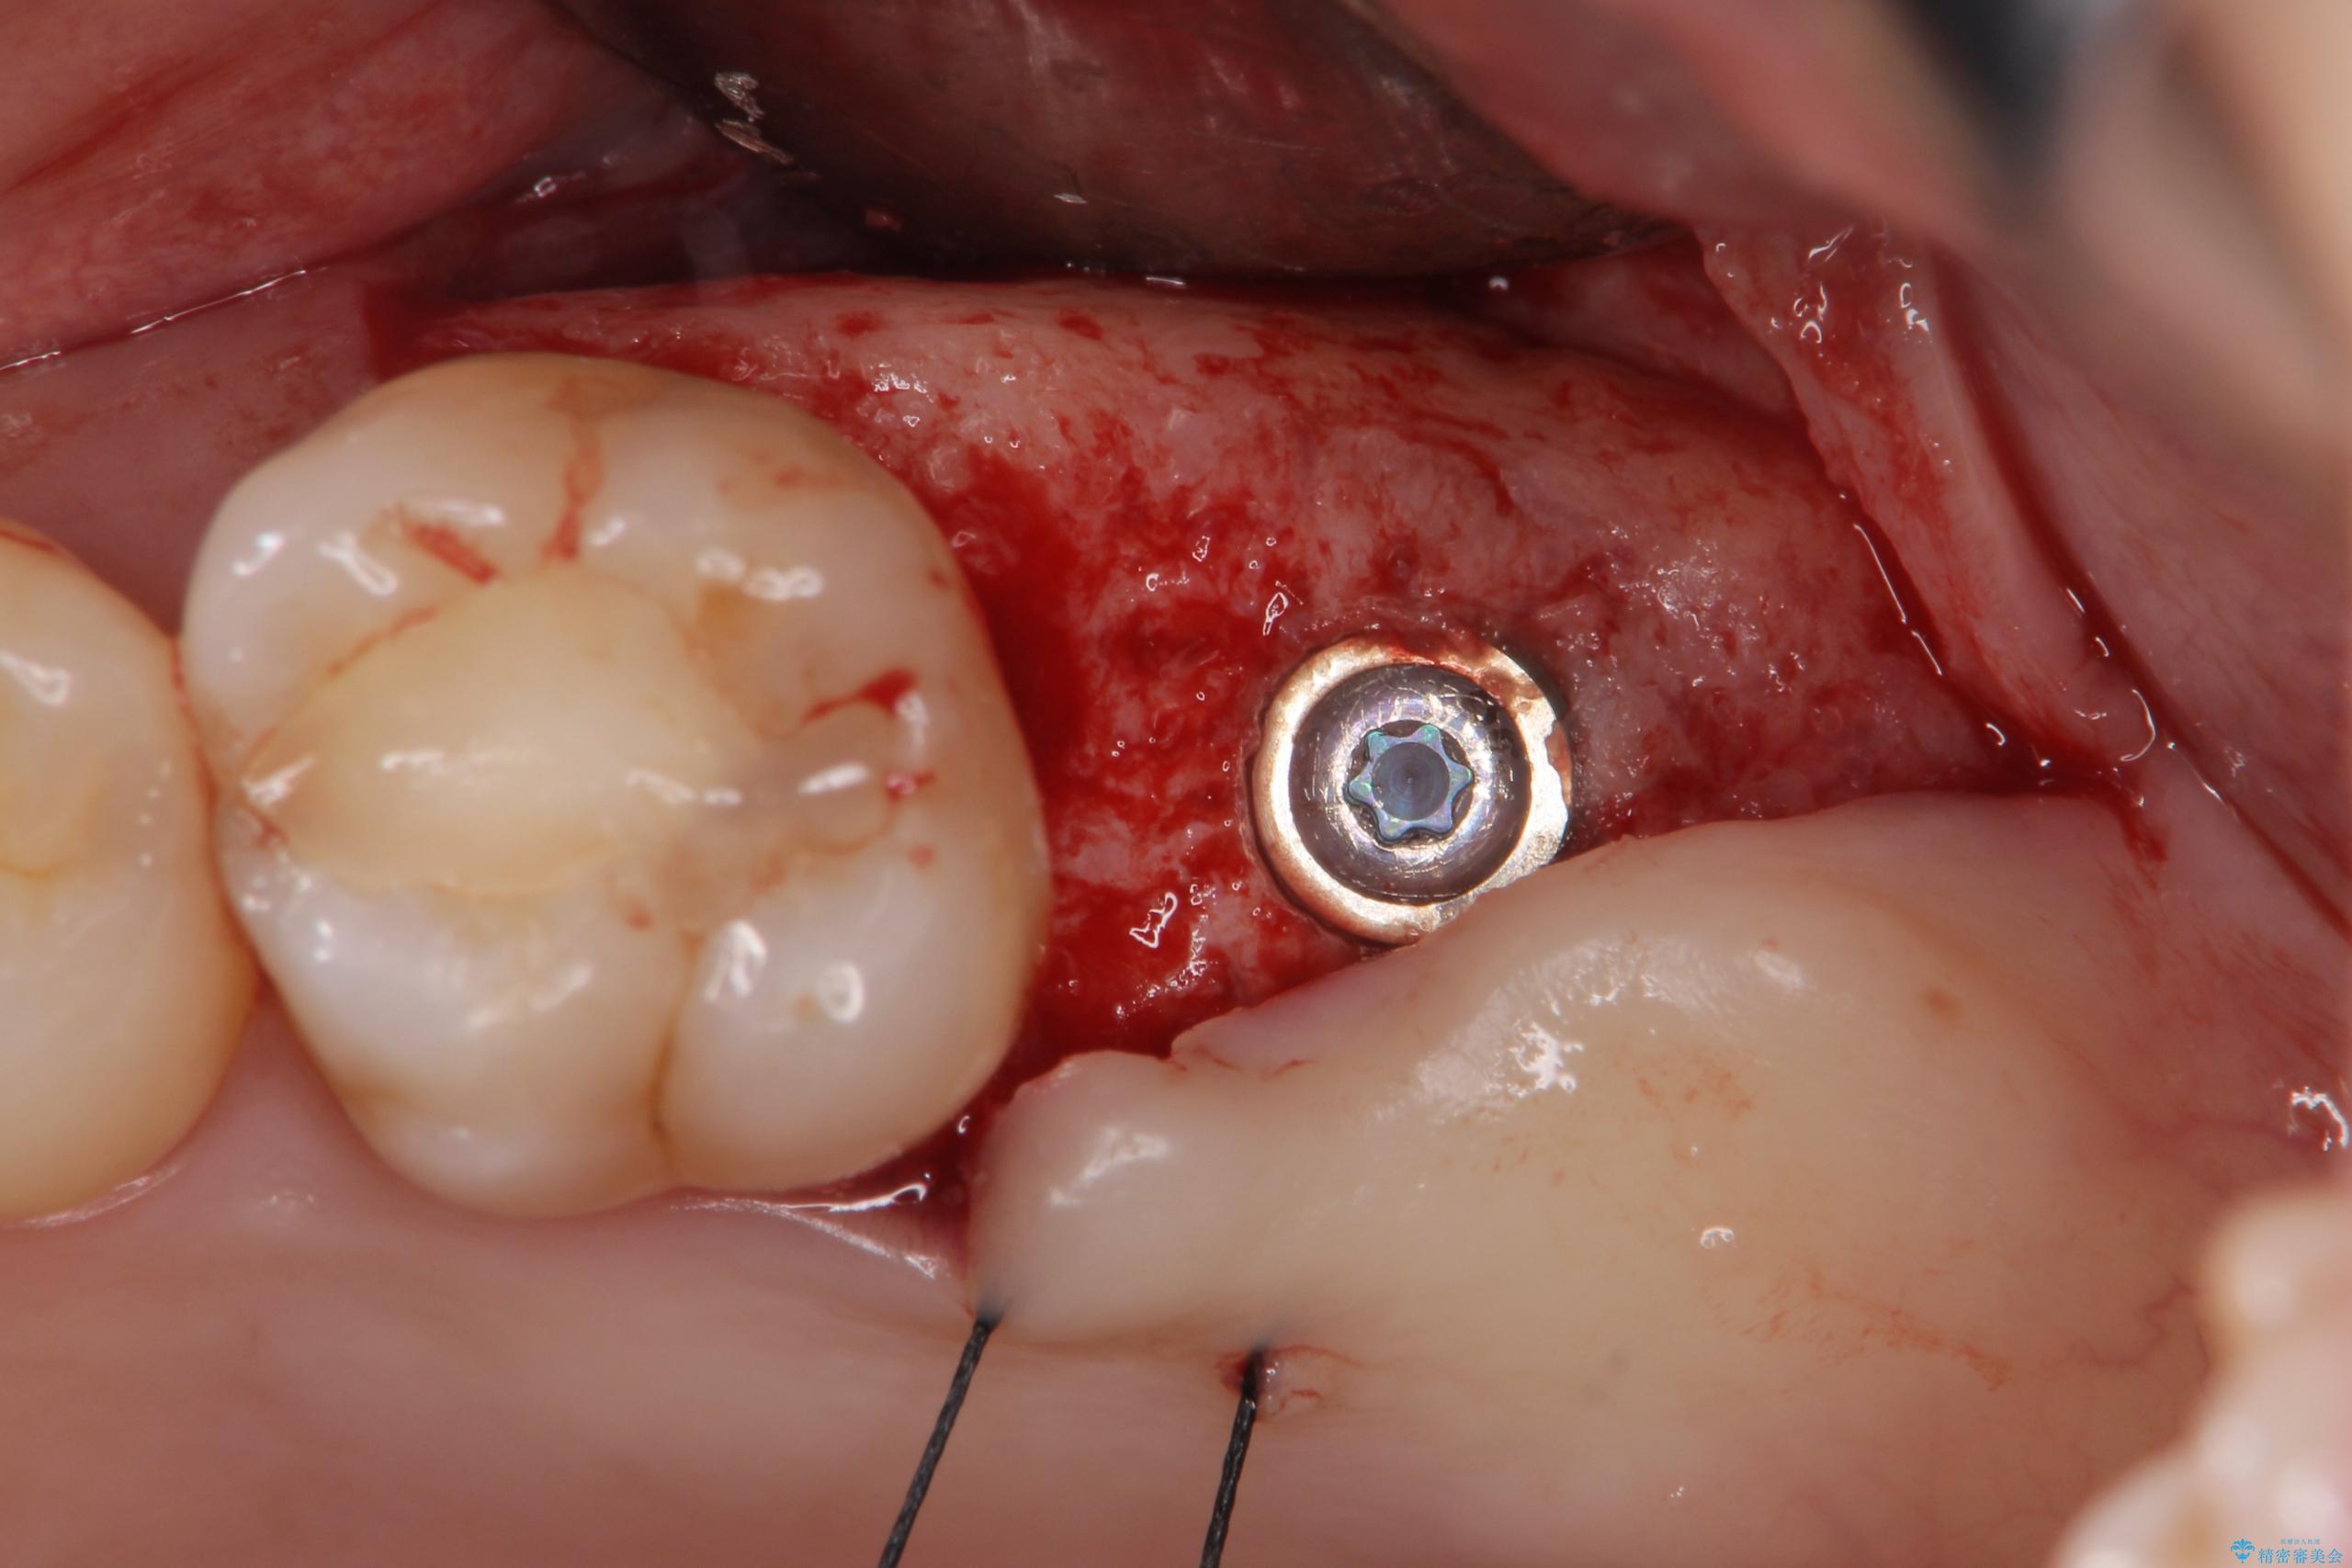

歯の抜去後、しっかりと咬合機能を回復するためインプラントを用いた治療を行っていきます。

治療中

【噛むと歯が疼く】歯牙破折からのインプラント治療 治療中画像 【噛むと歯が疼く】歯牙破折からのインプラント治療 治療中画像 【噛むと歯が疼く】歯牙破折からのインプラント治療 治療中画像 【噛むと歯が疼く】歯牙破折からのインプラント治療 治療中画像